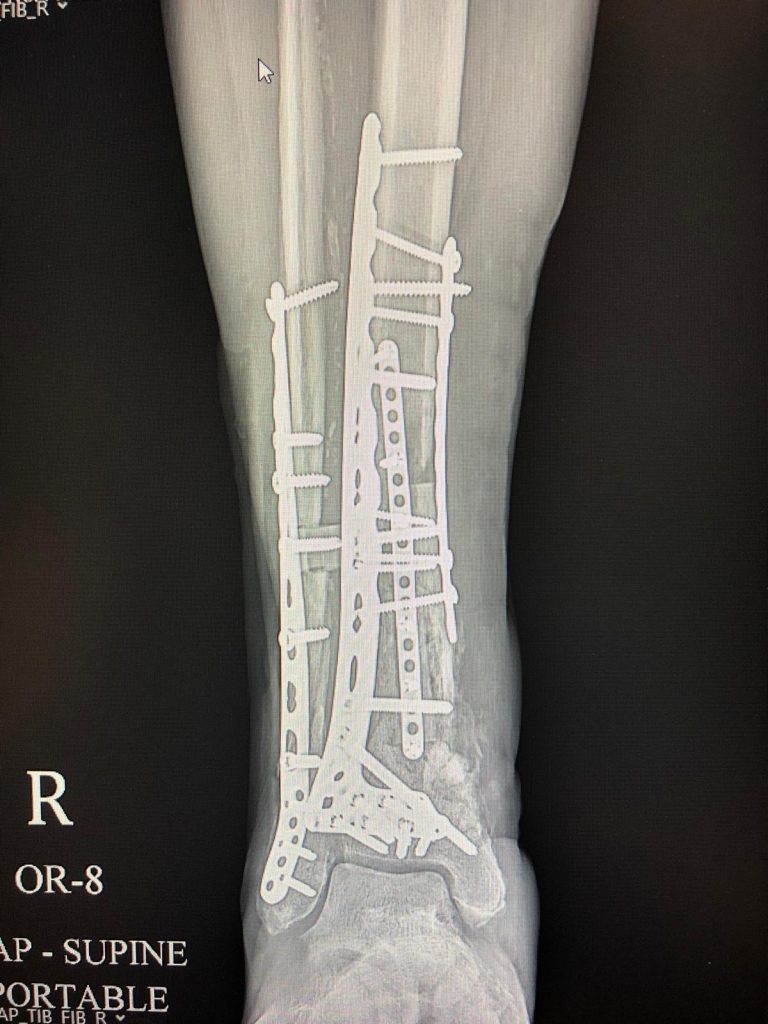

My mom fell and broke her leg in April of 2020 -- right at the height of the Covid-19 pandemic. We sought minimal treatment at the time so we could avoid having her in the hospital during. After months of rest and no luck with the break healing we went to HSS. We were extremely nervous at the thought of this lengthy surgery, as my mother is 76 years old. Dr. Campbell took the time to review all aspects of the surgery he planned to perform, and answer all of our questions with patience and professionalism. Our family went ahead with this procedure because Dr. Campbell showed great confidence in his ability to repair the leg and give my mom the highest chances of going on to walk again. After months of being casted and unable to walk, our family was both nervous and excited to hear that there was still hope of her returning to most of her pre-fall activities. I cannot say this enough, Dr. Campbell did an amazing job- we could not have wished for the procedure to go as great as it did. It has been 7 months since her surgery and while she is still building her strength back up, the work Dr. Campbell did to repair her breaks is stable and her most recent scans show that everything is on the mend. We simply cannot thank him enough for his masterpiece!